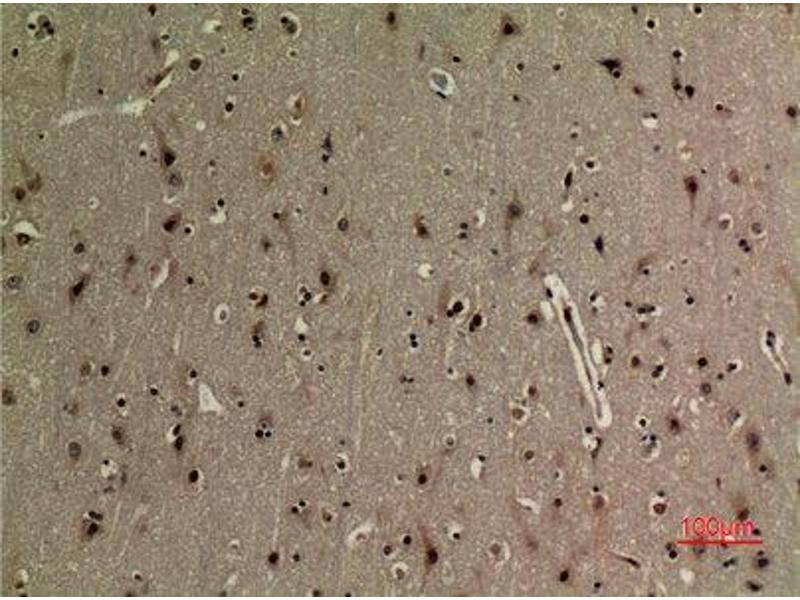

NFkBP65 Reaktivität: Human, Maus, Ratte WB, ELISA, IHC (p) Wirt: Kaninchen Polyclonal unconjugated

Produktnummer ABIN3188030

377,51 €